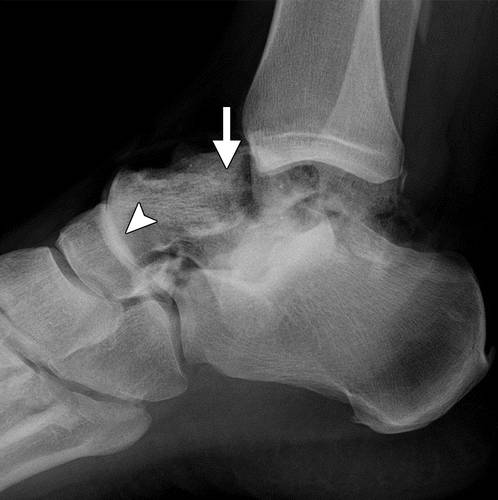

图10a粉碎性骨折冠状剪切距骨体断裂。 (a)该踝的外侧片显示距骨体(箭头)与在后距下关节突骨折碎片的冠剪切断裂。 (b)踝关节的AP射线照片显示后面小面(箭头)的揭示,与后股间关节的半脱位一致。 (c)矢状的CT图像显示了主要在冠状面中的距骨体的粉碎性骨折(箭头)。 在后距下关节处的骨折碎片存在前后牵引,导致半脱位(箭头)。

距骨体的剪切断裂通常由在高度跌倒或机动车辆事故的设置中的背屈脚上的轴向负载引起。 粉碎粉碎的距骨体外骨折对所有距骨损伤的预后最差(24)。 它们通常由于高能量冲击并且经常是开放性骨折。 骨丢失和非解剖复位的发生率高,并且随后出现缺血坏死。

初步诊断可以用放射线摄影,然后进行冠状和矢状重建到踝臼的CT,以评估粉碎,关节内累及手术计划(1,25,26)。